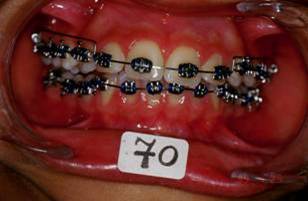

Je crois cette fois ca va marcher. Il s'agit d'une jeune fille de 12 ans, origine franco-libanaise, deja reglee depuis qqs mois. Classe II1 dentaire. Une demande majeure pour la patiente et sa maman: Les dents du haut sont trop en avant, il ne faut surtout pas les avancer ou les garder comme ca!!!

Voici les photos intermediaire apres: un QH, reeducation,propuleur Balters simple, multi-bague avec el II ancrage maxi bas, mini haut avec le trace. La maman et la patiente n'etaient pas d'accord du tout! Je comprends tout a fait leur point de vue... A suivre